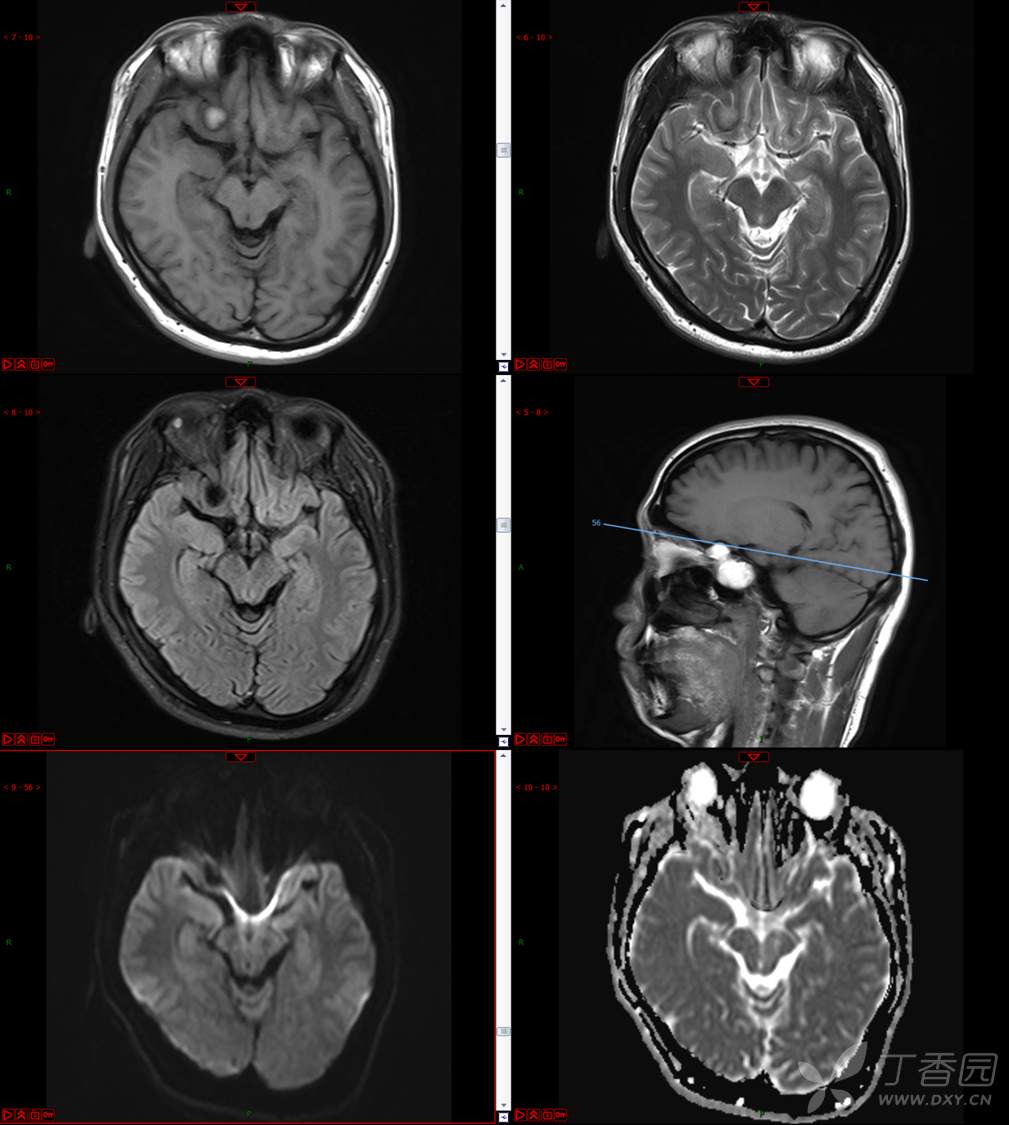

【影诊笔记534】青年男性,视物模糊就诊,CT、MRI、MRS齐全,请分析~~~

主 诉:视物重影5天。

现病史:患者5天前无明显诱因出现视物重影,表现为右视时视物成双,无头痛、头晕,无恶心、呕吐,无面部麻木、饮水呛咳等,于当地医院就诊,行颅脑MR示“颅内占位性病变”,现为求进一步治疗来诊。患者病来精神可,饮食、睡眠正常,体重无明显变化。